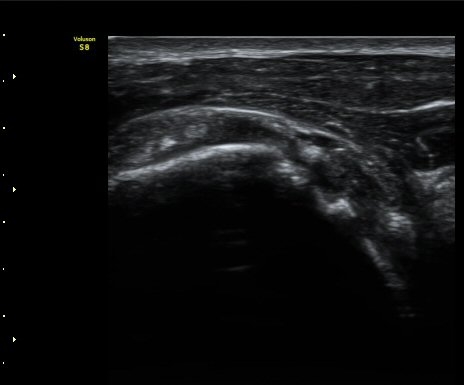

ÀÌµÎ¹Ú±Ù°Ç È¾´Ü¸é°Ë»ç¿¡¼­ °ÇÁÖÀ§¿¡ ¼Ò·®ÀÇ ¼ö¾×Àú·ù¿Í Á¡¾×³¶³» ¾×Àú·ù°¡ °üÂûµÈ´Ù(»çÁø 1, 2).